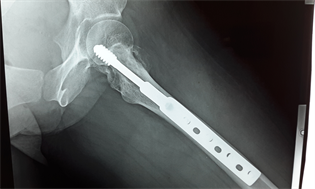

Mrs. SM, a 35-year-old patient consulted in the department for pain and dodge lameness of the left hip evolving for six months around. There was no notion of trauma. There was no specific pathological history. On examination, there was a pain awakened to the palpation supported by the greater trochanter and to the mobilization of the hip. The mobility of the joint was normal. The general condition was well preserved and the biological balance showed no abnormality. The standard X-ray of the frontal pelvis and the profile hip showed a circumscribed osteolytic image of the greater trochanter and of the femoral neck (Figure 1).

Figure 1. X-ray of the pelvis showing the tumor.